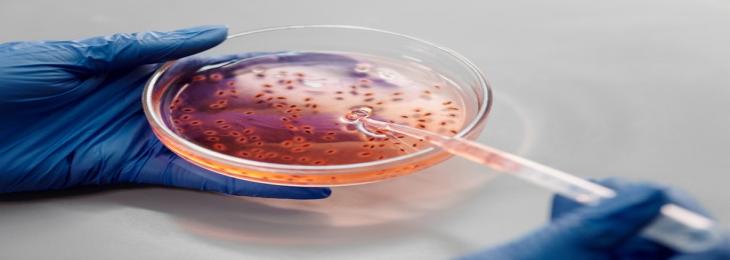

A new study found that specific type of gut bacteria hoard consumed drugs restricting their efficiency. There are numerous bacteri...

A new study found that specific type of gut bacteria hoard consumed drugs restricting their efficiency. There are numerous bacteri...